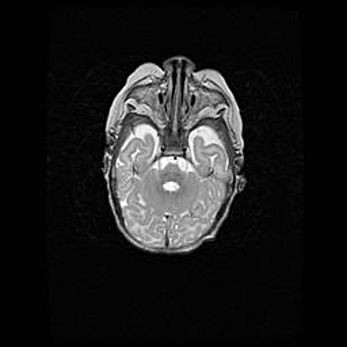

Церебральная ишемия II.

Возраст: 5 дней

Вес: 3400 г

Пол: женский

Окружность головы: 35 см

Срок гестации: 39 недель

Церебральная ишемия – это заболевание, характеризующееся недостаточностью (гипоксией) либо полным прекращением (аноксией) снабжения мозга кислородом по причине закупорки одного или нескольких сосудов. Это приводит к  что метаболическим расстройствам различной степени тяжести в тканях головного мозга, развитию коагуляционных некрозов и гибели нейронов.